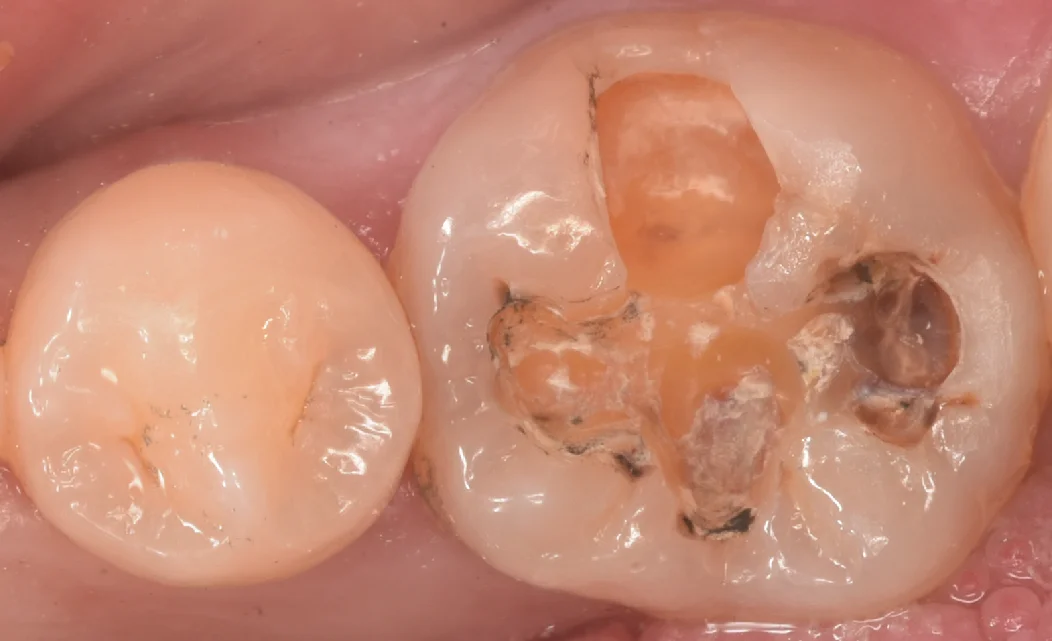

まずは術前からです。

今回は画面右側の保険の金属が入っている歯を治療していきます。

保険の金属の脇に隙間ができて、そこから虫歯が入り込んでいるのが画像上でもわかりますね。

金属を除去して内部のセメントを粗方とって虫歯を見やすくしたのがこちらになります。

非常にわかりづらいですが、画面上で上側の色が黄色っぽいところも全て虫歯になっている状態です。

臨床上で良く経験しますが、レントゲン上でそこまで大きくなくてもインレーを除去するとこのように内部で爆発的に虫歯が進行しているケースが多々あります。

定期検診で歯科医師にしっかりと確認してもらうのはもちろんとして、レントゲンなども定期的に撮影し、変化をしっかりと確認しておいた方が無難なのはこう言う部分もあります。

そして虫歯を取り切ったのがこちらになります。

歯の色が綺麗に出たのがわかるかと思います。

全体的にほぼ同じような色になっていますよね。